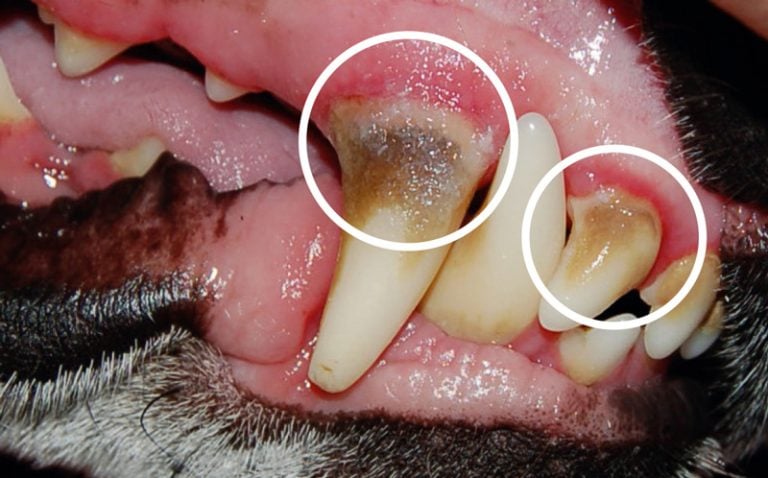

Pred začetkom zdravljenja

Pred začetkom zdravljenja z OralClean+Care, vidi se zobni kamen in vnete dlesni.

Po 2 mesecih uporabe

Po 2 mesecih je OralClean+Care odstranil zobni kamen in zmanjšal vnetje dlesni.